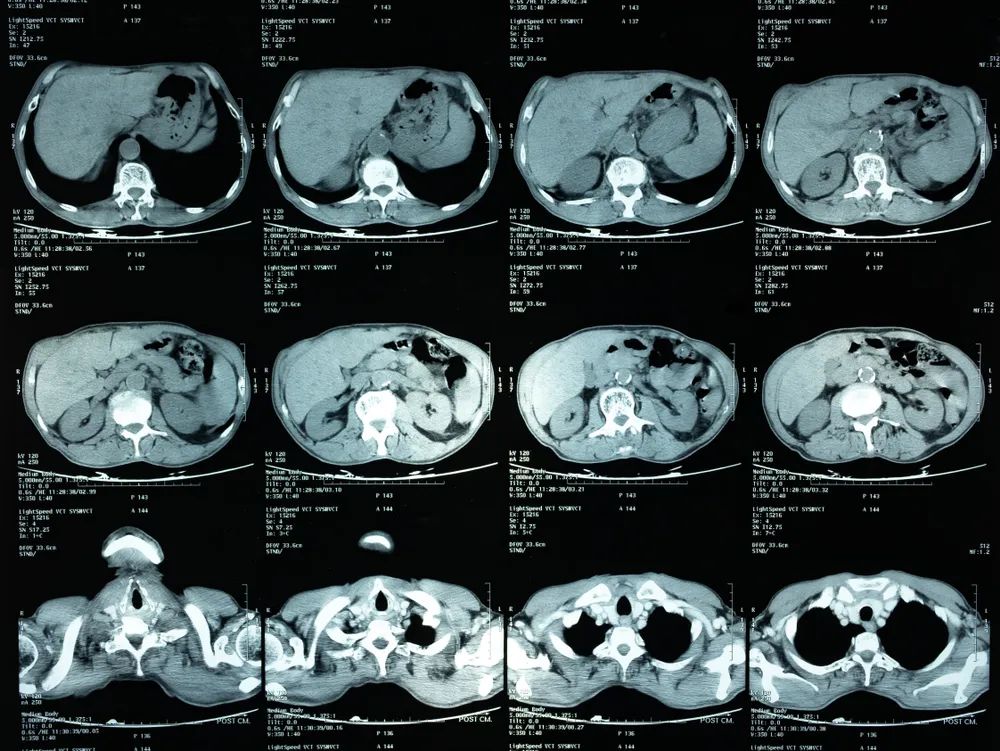

通过复杂计算,它可以把人体的横断面图片展示出来:

一个二维世界的生物看咱们的身体,估计就是这样一片一片的。

图片来源:站酷海洛

然后接下的场面通常是,医生指着一坨黑黑白白的东西向患者讲解,患者若有所思(假装听懂了

)。

CT 的好处在于避免了层叠图像的干扰,图像更加清晰且分辨率高。它还可以合成一个三维立体图像,相当于给你的身体建个模,对于疾病诊断和手术规划可太重要了。